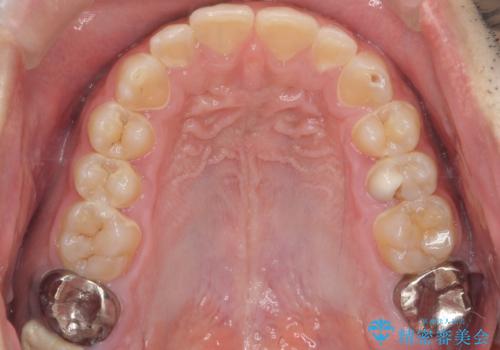

総合歯科治療 → 歯周病治療&インプラント治療

歯がボロボロで咬合崩壊 矯正・インプラント・セラミックで実現する、酸蝕症の総合治療